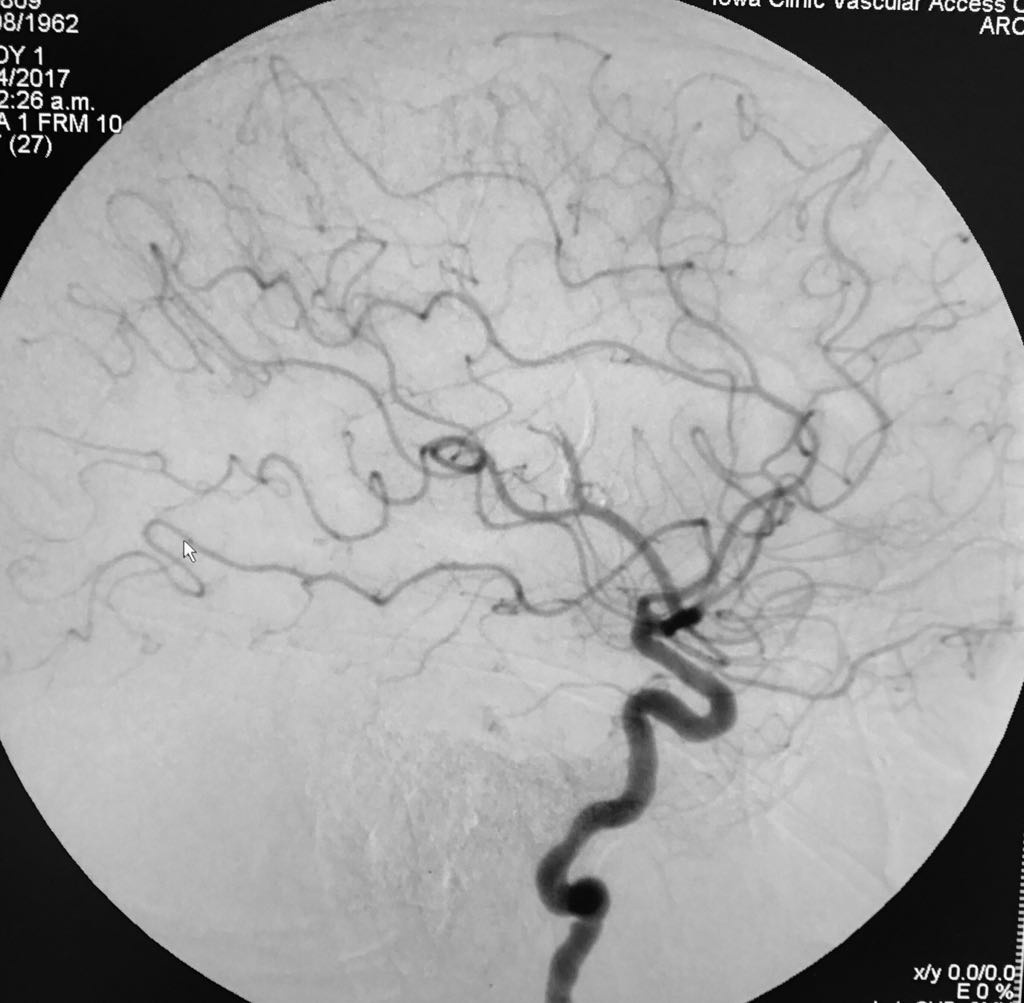

Somos una empresa enfocada en la atención en salud humana por medio del uso imágenes para ver diagnosticos y tratamientos de las diversas patologías con el uso de técnicas mínimamente invasivas en el territorio colombiano en el sector público y privado en búsqueda de una atención oportuna y de calidad a cada uno de nuestros pacientes.